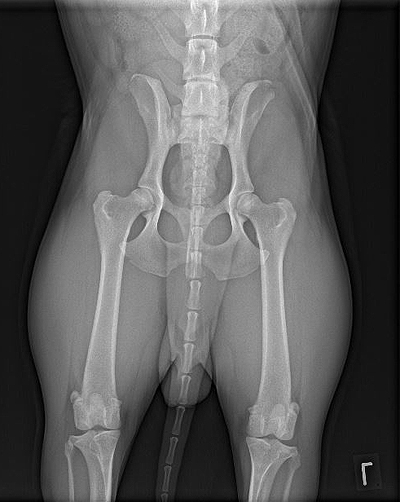

HD-Rö.-Aufnahme: Quitman ex Chelsea

HD-Röntgenbild: Preston ex Chelsea